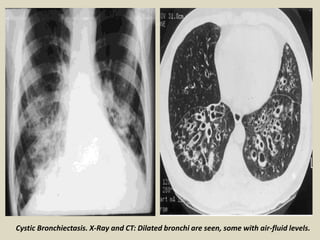

Cystic Bronchiectasis. X-Ray and CT: Dilated bronchi are seen, some with air-fluid levels.

Cystic Bronchiectasis.